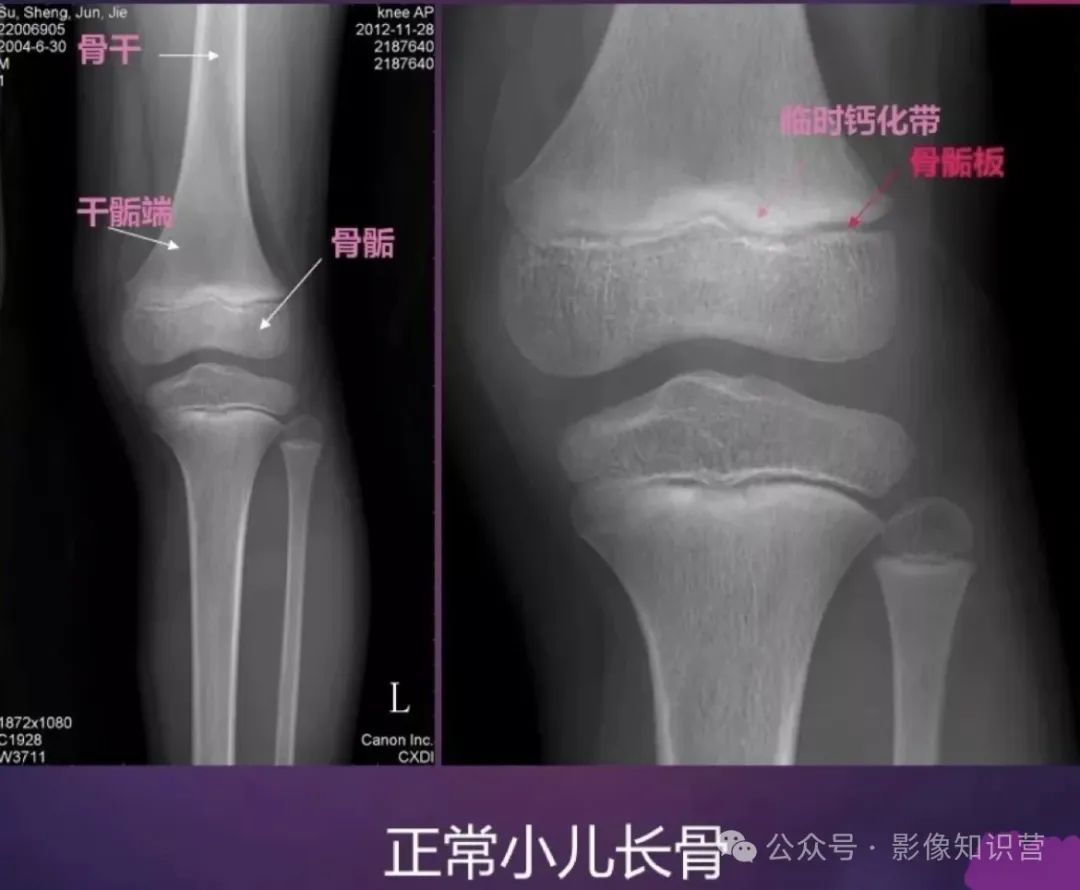

膝关节骨骼组成:股骨远端、胫骨近端、髌骨。

影像特征:X线侧位:观察髌骨位置及关节间隙(正常约3-5mm)。MRI可评估半月板(内“C”形、外“O”形)、交叉韧带及软骨损伤。